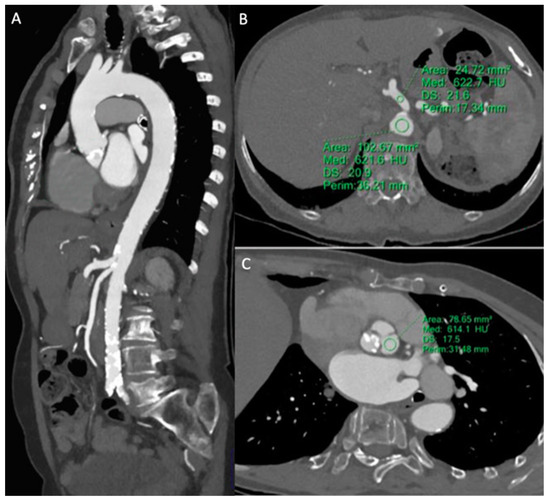

3.2.3. Pre-TAVR CTA